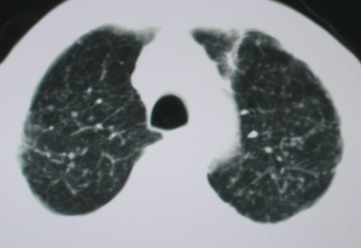

以下是引用卜一在2008-6-3 19:33:00的发言:[br]双肺结节,以双上肺分布为多,期间搀杂片状致密影及索条致密影。考虑:继发性肺结核伴血型播散可能性大。不除外肺泡ca的可能!另:椎体退变!

以下是引用医影拾贝在2008-6-3 18:48:00的发言:[br]双上肺弥漫性小结节影,纵隔窗内钙化淋巴结影,考虑血播性tb可能性较大,不除外肺ca可能

以下是引用panyishengct在2008-6-3 21:09:00的发言:[br]双上肺弥漫性小结节影,纵隔窗内钙化淋巴结影,考虑矽肺或/和tb可能性较大,不除外肺ca可能。腰椎考虑退变。 [br][br]